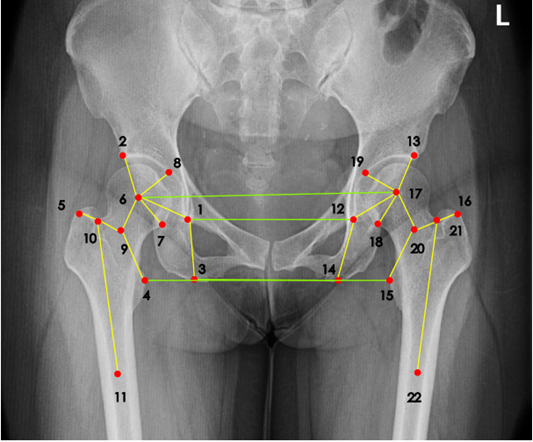

那么有没有可能通过某些自动化方法或者软件来完成准确而且标准的髋关节置换规划?答案是可行的。2018年左右,来自约翰霍普金斯大学的学者曾经提出通过两阶段卷积神经网络结构(CNN)来检测X射线成像图谱的手术测量标志点,并且能够从任意角度来完成成像检测。同时,也有有其他的一些研究试图引入人体解刨学特点,通过找到原本手术测量标志点之间的关系自动标注。但是在实践环节中,这些方法的准确率相较传统方案,并没有提升太多。

达摩院团队认为,医疗图像里不仅仅可以检测标志点,而且能同时自动学习这些手术测量标志点之间的关系,比如可以通过添加一个标志点的空间关系损失函数,来获得更加精确且高效的手术测量标志点检测结果。这种思想也就是把传统神经网络分别为两个支路:一个标志点预测分支,另一个边缘预测分支。在这种思想下,图像会先通过神经网络处理,再分别输入两个分支做不同目的的推理。其中标签预测分支将会把神经网络处理过后的高维特征转换为热点图,而边缘预测分支将会把神经网络处理过的边缘高维特征降维,此后向量化的标记将会提取更好的特征,这样可以通过一个专门针对标识空间位置建立的损失函数来提高边缘标签预测的准确度。